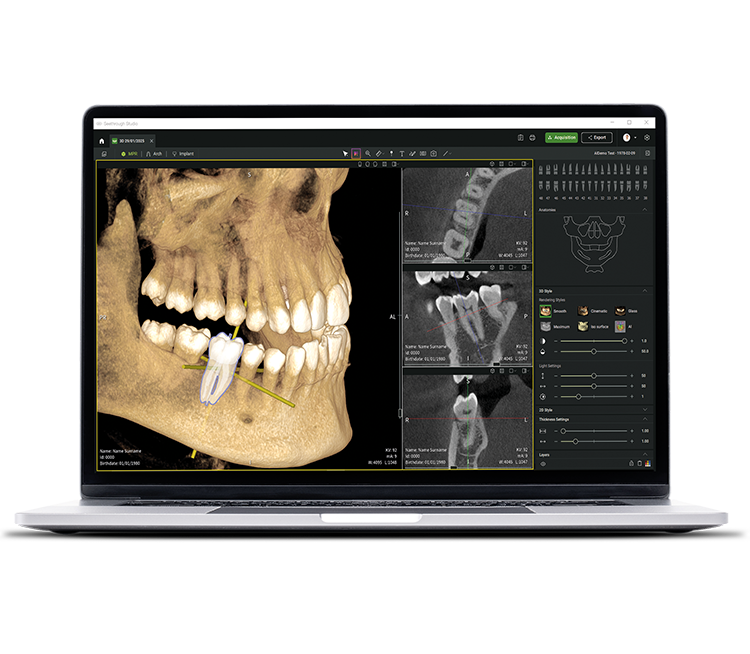

Neben ausgereiften Hardware-Technologien ist die revolutionäre Seethrough Studio Software der entscheidende Faktor für den hohen Standard des gesamten W&H-Imaging Portfolios: Mit nützlichen Funktionen und fortschrittlichen Algorithmen ist Seethrough Studio eine Komplettlösung, die die Bildgebung und digitale Workflows in der Zahnmedizin auf ein neues Niveau hebt.

Integriertes Implantatplanungstool

Über die herausragende Bildqualitätund die intuitive Bedienung hinaus bietet Seethrough Studio zahlreiche nützliche Funktionen wie etwa das standardmäßig integrierte Implantatplanungstool für eine einfache Visualisierung und Vorbereitung der Behandlung.

KI-unterstützte Funktionen

Seethrough Studio nutzt verschiedene KI-Tools für eine noch bessere Bildgebung wie 3D-Volumenausrichtung, Zahnsegmentierung, Bogenliniengenerierung, automatische Nervenerkennung und hilfreiche Unterstützung bei der Pathologieerkennung.